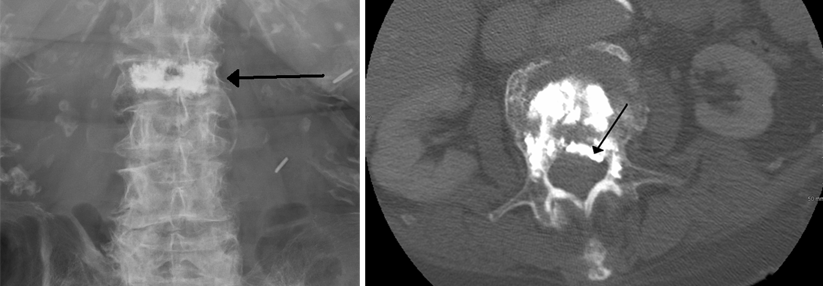

Sehen Sie dann, dass ein Patient bei jedem Besuch in der Praxis kleiner zu werden scheint, eine Kyphose entwickelt oder über akute, lokalisierte Rückenschmerzen klagt, wird es Zeit die Diagnostik…